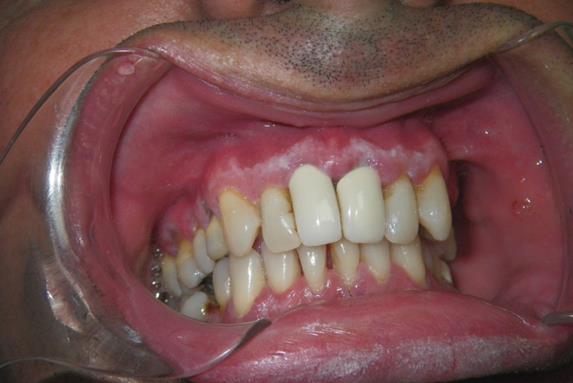

Si encontraste una anomalía en tus encías, paladar, dientes o labios, es necesario acudir a examinarte la lesión, evitando que esta se desarrolle y avance a más complicaciones en el futuro. La principal razón de las alteraciones de la encía son las bacterias, pero hay que saber que existen lesiones que son la manifestación de problemas que se pueden detectar cuando están iniciando y que se relacionan con enfermedades dermatológicas, con las hormonas, medicamentos, virus, hongos, discrasias sanguíneas, alteraciones oncológicas o, genéticas.

Estas patologías se pueden manifestar como lesiones blancas, lesiones rojas, ulceraciones o, tumoraciones.